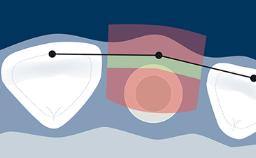

Structured Assessment and Treatment Planning

Esthetic Risk Assessment

Learning Module